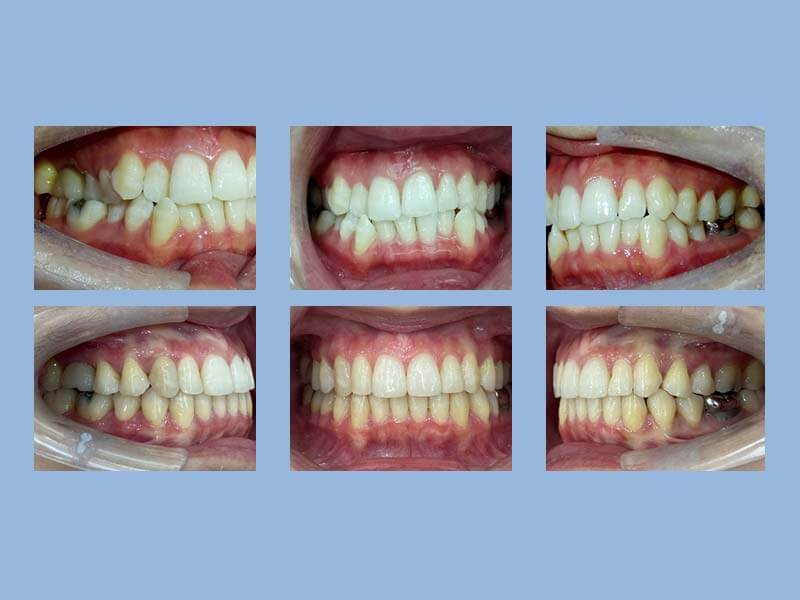

余先生 (20歲) 矯正完成

狀態 : 第二套完成照、暴牙、牙齒擠、沒拔牙